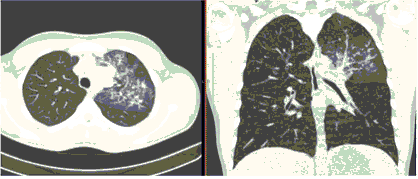

- Изменения при КТ (рентгенографии), типичные для вирусного поражения (объем поражения минимальный или средний; КТ 1-2)

- Изменения в легких при КТ (рентгенографии), типичные для вирусного поражения (объем поражения значительный или субтотальный; КТ 3-4)

- Изменения в легких при КТ (рентгенографии), типичные для вирусного поражения критической степени (объем поражения значительный или субтотальный; КТ 4) или картина ОРДС.

КТ имеет высокую чувствительность в выявлении изменений в легких, характерных для COVID-19. Применение КТ целесообразно для первичной оценки состояния ОГК у пациентов с тяжелыми прогрессирующими формами заболевания, а также для дифференциальной диагностики выявленных изменений и оценки динамики процесса. КТ позволяет выявить характерные изменения в легких у пациентов с COVID-19 еще до появления положительных лабораторных тестов на инфекцию с помощью МАНК. В то же время, КТ выявляет изменения легких у значительного числа пациентов с бессимптомной и легкой формами заболевания, которым не требуется госпитализация. Результаты КТ в этих случаях не влияют на тактику лечения и прогноз заболевания при наличии лабораторного подтверждения COVID-19. Поэтому массовое применение КТ для скрининга асимптомных и легких форм болезни не рекомендуется.

3. Применение лучевых методов у пациентов с симптомами ОРВИ легкой степени тяжести и стабильном состоянии пациента, возможно только по конкретным клиническим показаниям, в том числе при наличии факторов риска, при условии достаточных технических и организационных возможностей. Методом выбора в этом случае является КТ легких по стандартному протоколу без внутривенного контрастирования или РГ при ограниченной доступности КТ. Использование УЗИ в этих случаях нецелесообразно.

5. Рекомендовано проведение лучевого исследования пациентам при среднетяжелом, тяжелом и крайне тяжелом течении ОРИ с целью медицинской сортировки, оценки характера изменений в грудной полости и определения прогноза заболевания:

- выполнение КТ легких без внутривенного контрастирования в стационарных условиях или в амбулаторных - при показаниях к госпитализации;